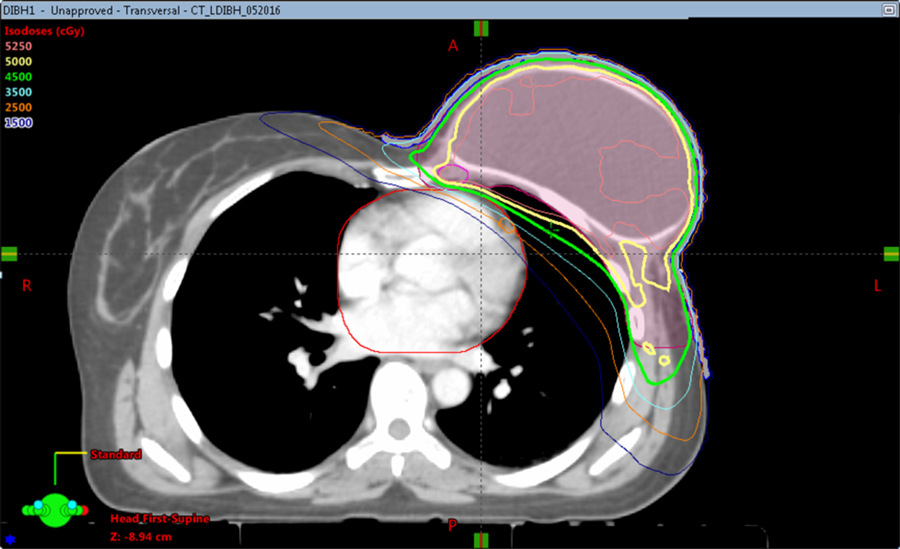

一种用来尽量减少器官暴露于不必要辐射的技术是深吸气屏息(DIBH)。DIBH是一种与传统3D适形放疗相结合的治疗乳腺癌的技术。在这种技术中,患者深呼吸,增加胸壁和心脏之间的距离,扩大肺容量,以及增加治疗区域和其他正常组织之间的距离。由于病人会屏住呼吸,这也有助于他们在放射过程中保持静止。

杜曼和同事博士最近发表了一项研究调查DIBH在使用VMAT时减少低剂量暴露于降低临界器官的临界器官,以及使用VMAT的其余部分。在该研究中重点的患者经历了含有组织膨胀器或永久性植入物的乳房切除术,并在传统的3D全成形技术中提供解剖学复合物的治疗解剖学复合物。因此,VMAT是这些患者的首选,因为3D技术将在高剂量辐射暴露的显着风险下将其关键的器官置于其临界器官。

在研究中,预先确定了左侧乳腺癌这样的患者进行了研究。为了量化使用VMAT的DIBH减少低剂量暴露,计算患者的辐射剂量,并比较两种不同模式,即自由或常规呼吸和DIBH获得的CT扫描。在Dibh期间,妇女被要求在20秒内深呼吸约20秒,在他们的模拟和治疗之前在家练习这一点,以提高他们呼吸呼吸并最大化肺部的能力的能力和信心并持有大呼吸。

使用VMAT和DIBH的组合将辐射减少到心脏和肺部分别30%和11%,并将对侧乳腺/植入物分18%。

Dumane博士总结道,由于复杂的解剖结构,当需要植入物重建也需要局部淋巴结放疗的乳腺癌患者接受VMAT治疗时,应该考虑DIBH。VMAT和DIBH联合使用,对心脏和肺的辐射分别减少了30%和11%,对侧乳房/植入物的辐射减少了18%。这表明使用呼吸是有益的,应该考虑到治疗计划为这个病人组,特别是限于没有风险,和治疗中心与机器配置为使用这项技术应该不需要更多的专门培训或资源。